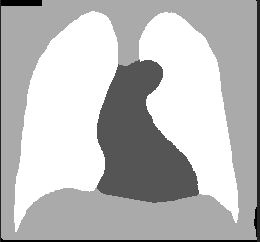

こちらの図のように、身体・肺・心臓・背景のように分割したい場合に、U-Netを使って学習させたモデルがどのぐらい領域分割できるか試してみます。